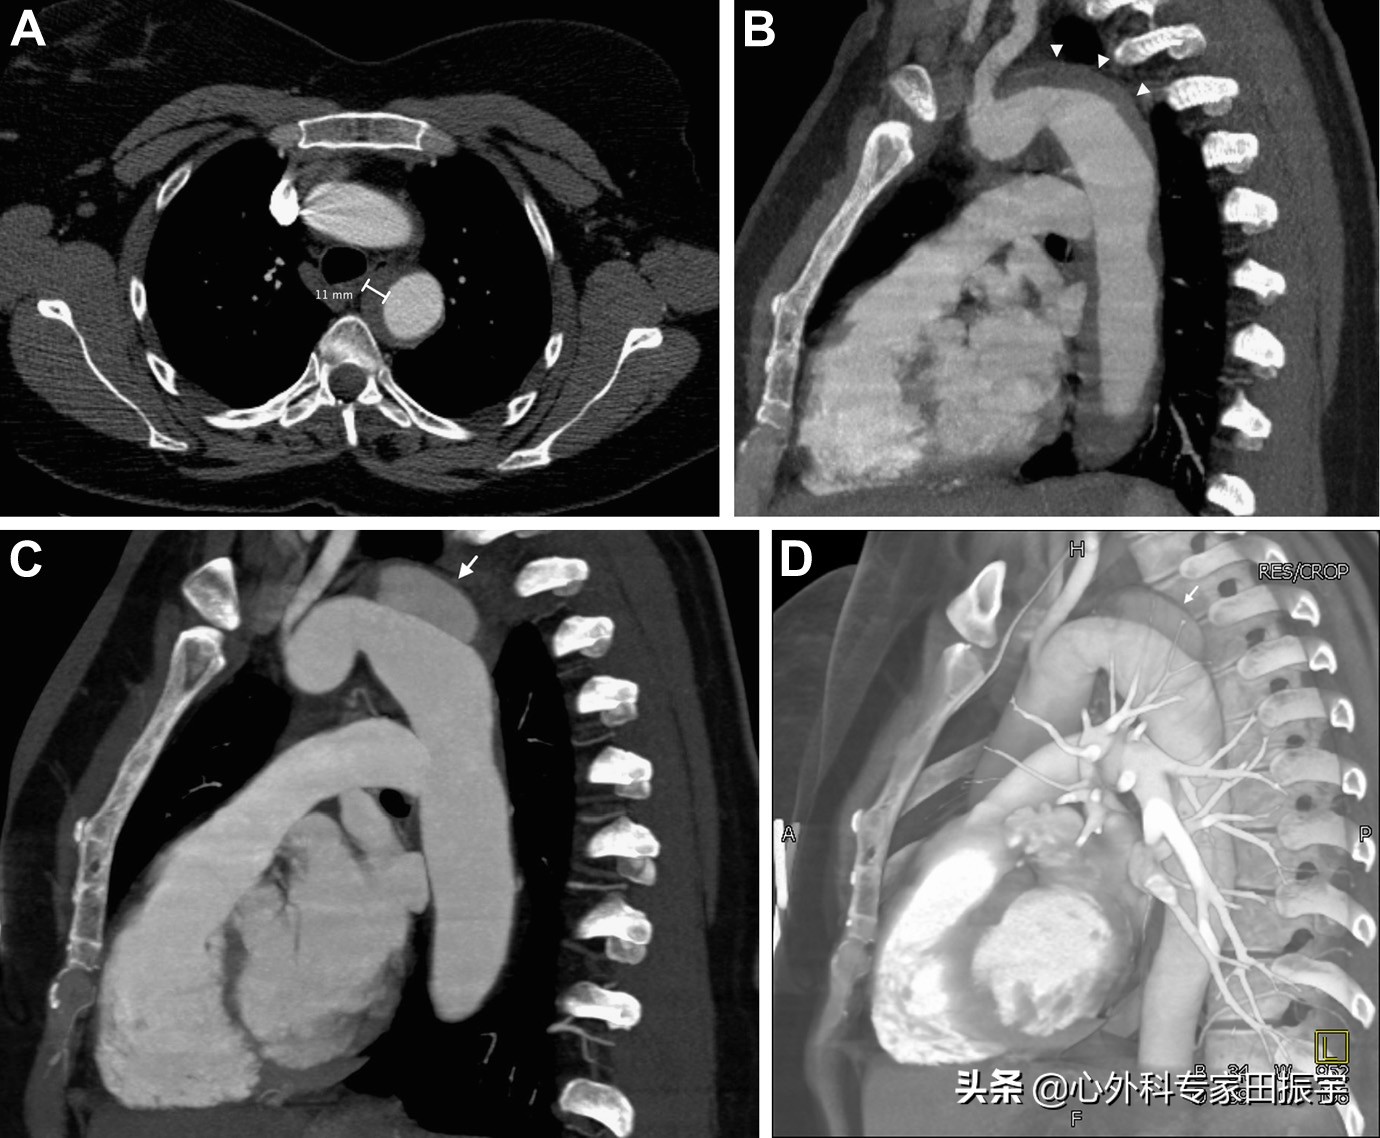

主动脉壁间血肿

图4 一名43岁妇女出现急性背痛和高血压危象。增强CT的轴向(A)和矢状多平面重建(B)CT 图像显示 B 型壁间血肿,血肿厚度为 11 mm(箭头)。3 个月后随访增强CT多平面重建图像(C)和三维体积重建图像(D)显示主主动脉弓远心端发展成假性动脉瘤(箭头)。